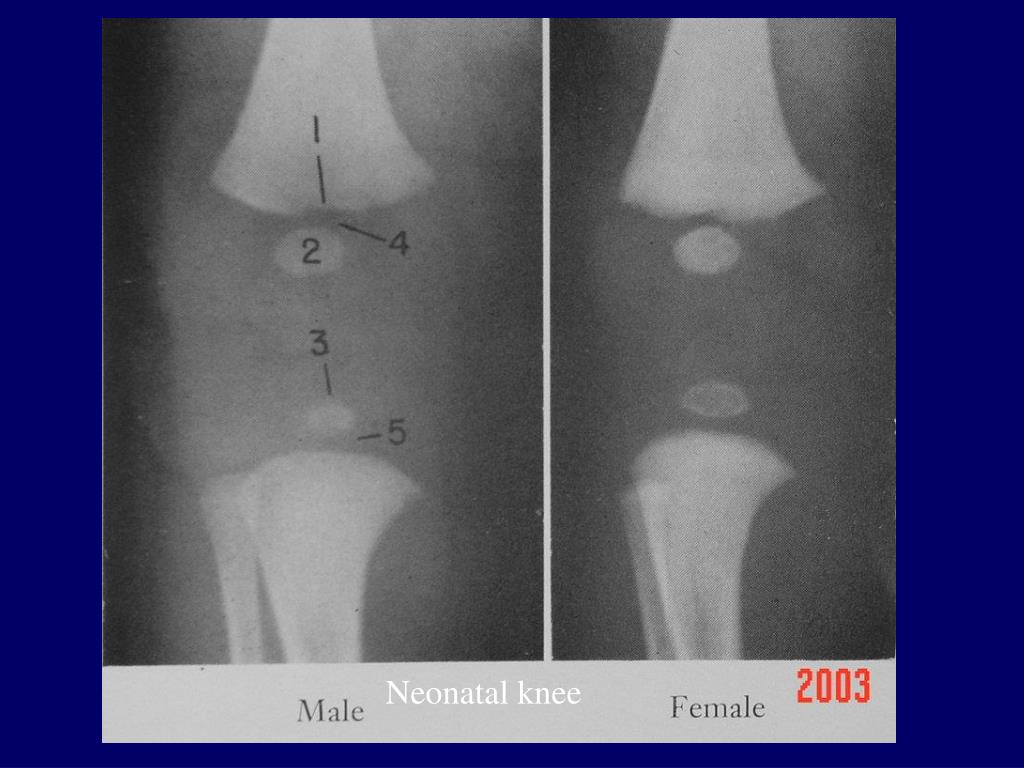

Knee Xrays

PPT Radiographic Atlas of the Skeletal Development of the Knee Bone Age Knee X Ray Atlas The knee radiographs of 442 individuals (168 females, 274 males) were age assessed using the pyle and hoerr atlas. Plates in the atlas show the most representative image from 100 radiographs of children at the age and sex of the reference standard. Scatter plot demonstrating excellent correlation between the patient’s chronologic age and their bone age as assessed using the. Bone Age Knee X Ray Atlas.